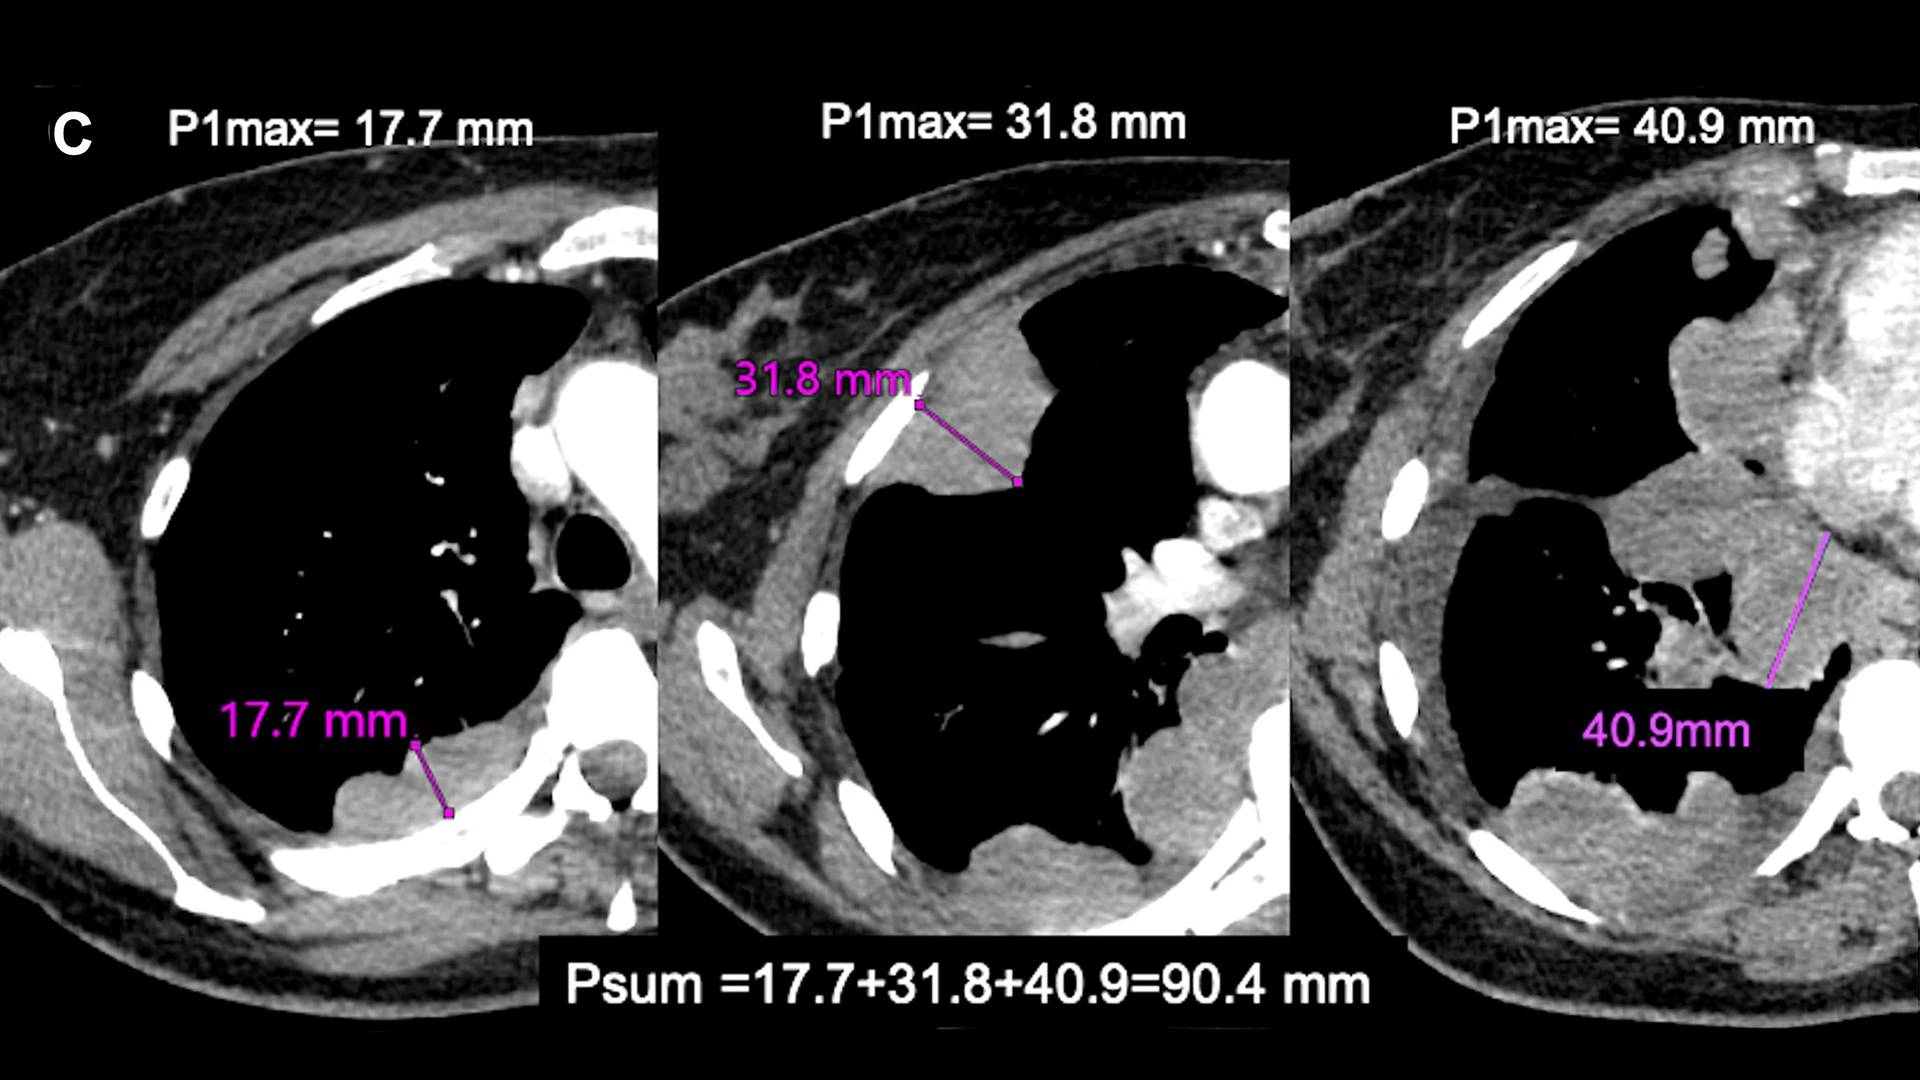

Coronal and sagittal images of patients with pleural mesothelioma illustrating division of the chest into approximate thirds by a line drawn at the level of the aortic arch and a second line at the top of the left atrium, dividing the chest into three relatively equal parts of upper, middle, and lower levels. The maximum pleural thickness on each of these levels (Pmax1, Pmax2, and Pmax3) is measured and combined to derive a sum of maximum pleural thickness (Psum=Pmax1 + Pmax2 + Pmax3).

3. Axial images with maximal pleural thickness measurement at each of the three levels; P1max=17.7 mm; P2max=31.8 mm and P3max=40.9 mm, and Psum=17.7 + 31.8 + 40.9=90.4 mm